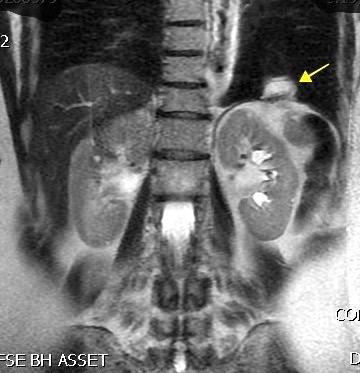

Autotrasplante de tejido esplénico al tórax tras trauma. (T. Penetrante más frecuente que cerrado)

T1: Hipointenso

T2: Hiperintenso. Puede ser hipointenso. (Hierro)

Esplenectomía previa

Ferrer TM et al. Thoracic splenosis: History is the key. Respiratory Medicine Case Reports. 2017